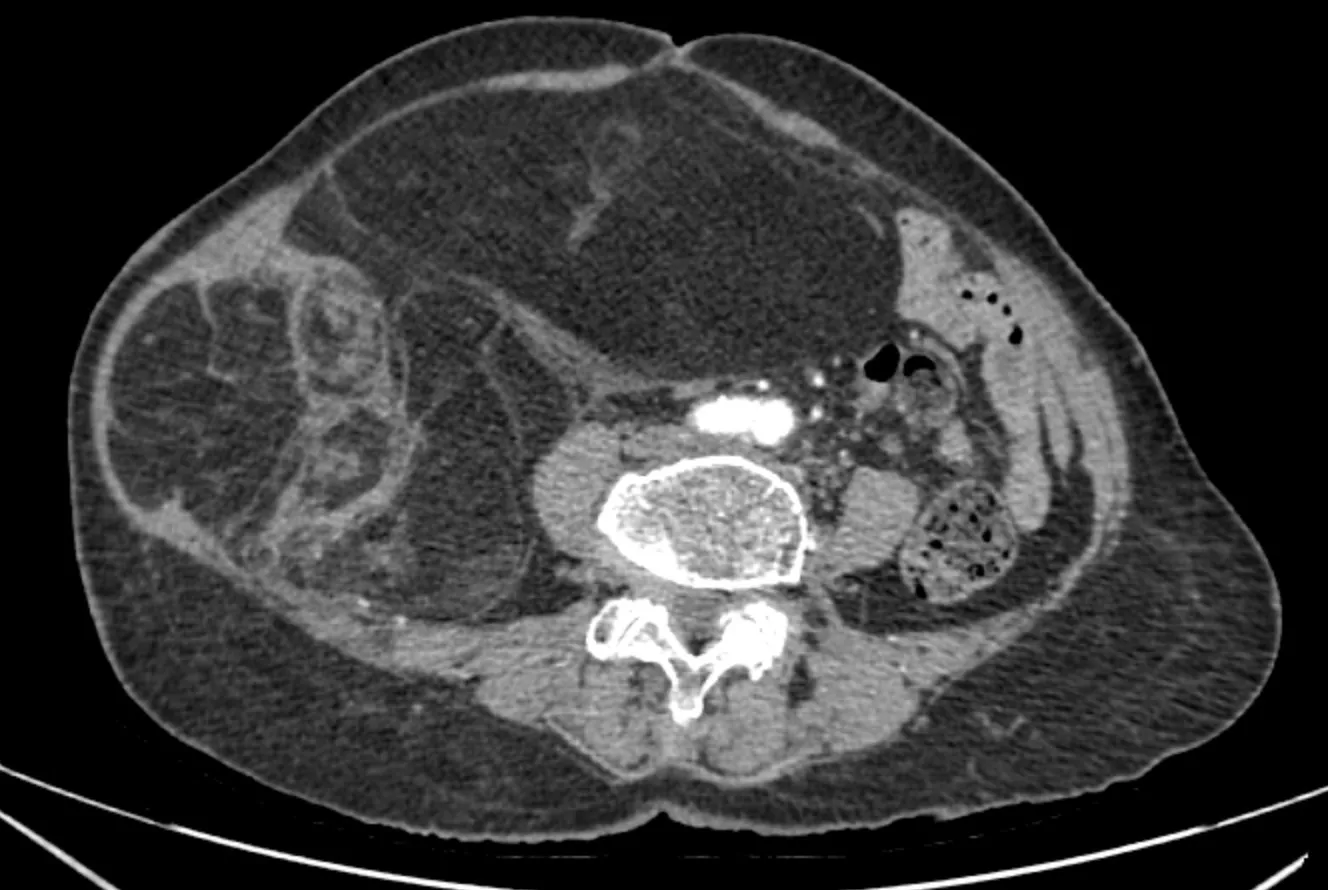

Hasil pencitraan diagnostik (CT scan abdomen dengan kontras) menunjukkan massa retroperitoneal berukuran 28 x 15 cm, struktur campuran lemak dan jaringan padat, menekan organ abdomen tetapi tidak menunjukkan tanda-tanda invasi ke organ di sekitarnya. Dengan menggabungkan pemeriksaan klinis dan pencitraan, pasien didiagnosis menderita liposarkoma retroperitoneal.

CT scan abdomen pasien NTT